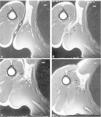

Se sospita l'existència de ruptura de l'LD o TM, per la qual cosa se sol·licita ressonància magnètica (fig. 3). S'observa una alteració del senyal al nivell de la inserció proximal del tendó de l'LD, amb ruptura fibril·lar completa i retracció del cos del múscul, edema i hematoma localitzat a la regió axil·lar.

Figura 3 Imatges de ressonància magnètica seriades axials en T1, en la regió axilar. S'observa el marcador cutani (m) amb fletxes que indiquen desestructuració en la zona de lesió. Retracció muscular del Latissimus dorsi (estels blancs).